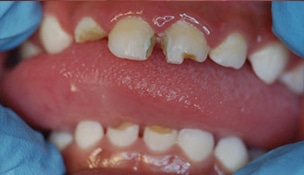

Severe ECC (S-ECC) is defined as any sign of smooth-surface caries in children younger than age 3. Additionally, in children ages 3 through 5, one or more dmf surfaces in primary maxillary anterior teeth, or a dmf score of ≥ 4 (age 3), ≥ 5 (age 4), or ≥ 6 (age 5) surfaces also constitutes S-ECC.3 The typical early sign of ECC is the crescent shaped white spot lesion at the gingival margin (Figure 1 to Figure 4).